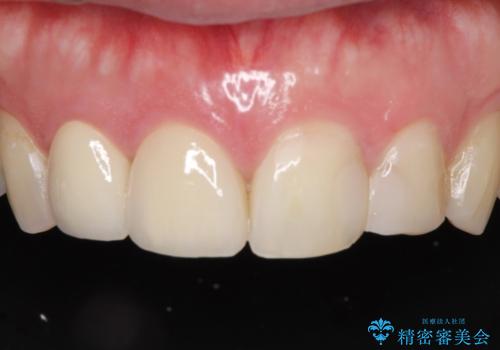

前歯の治療。再根管治療~セラミッククラウン